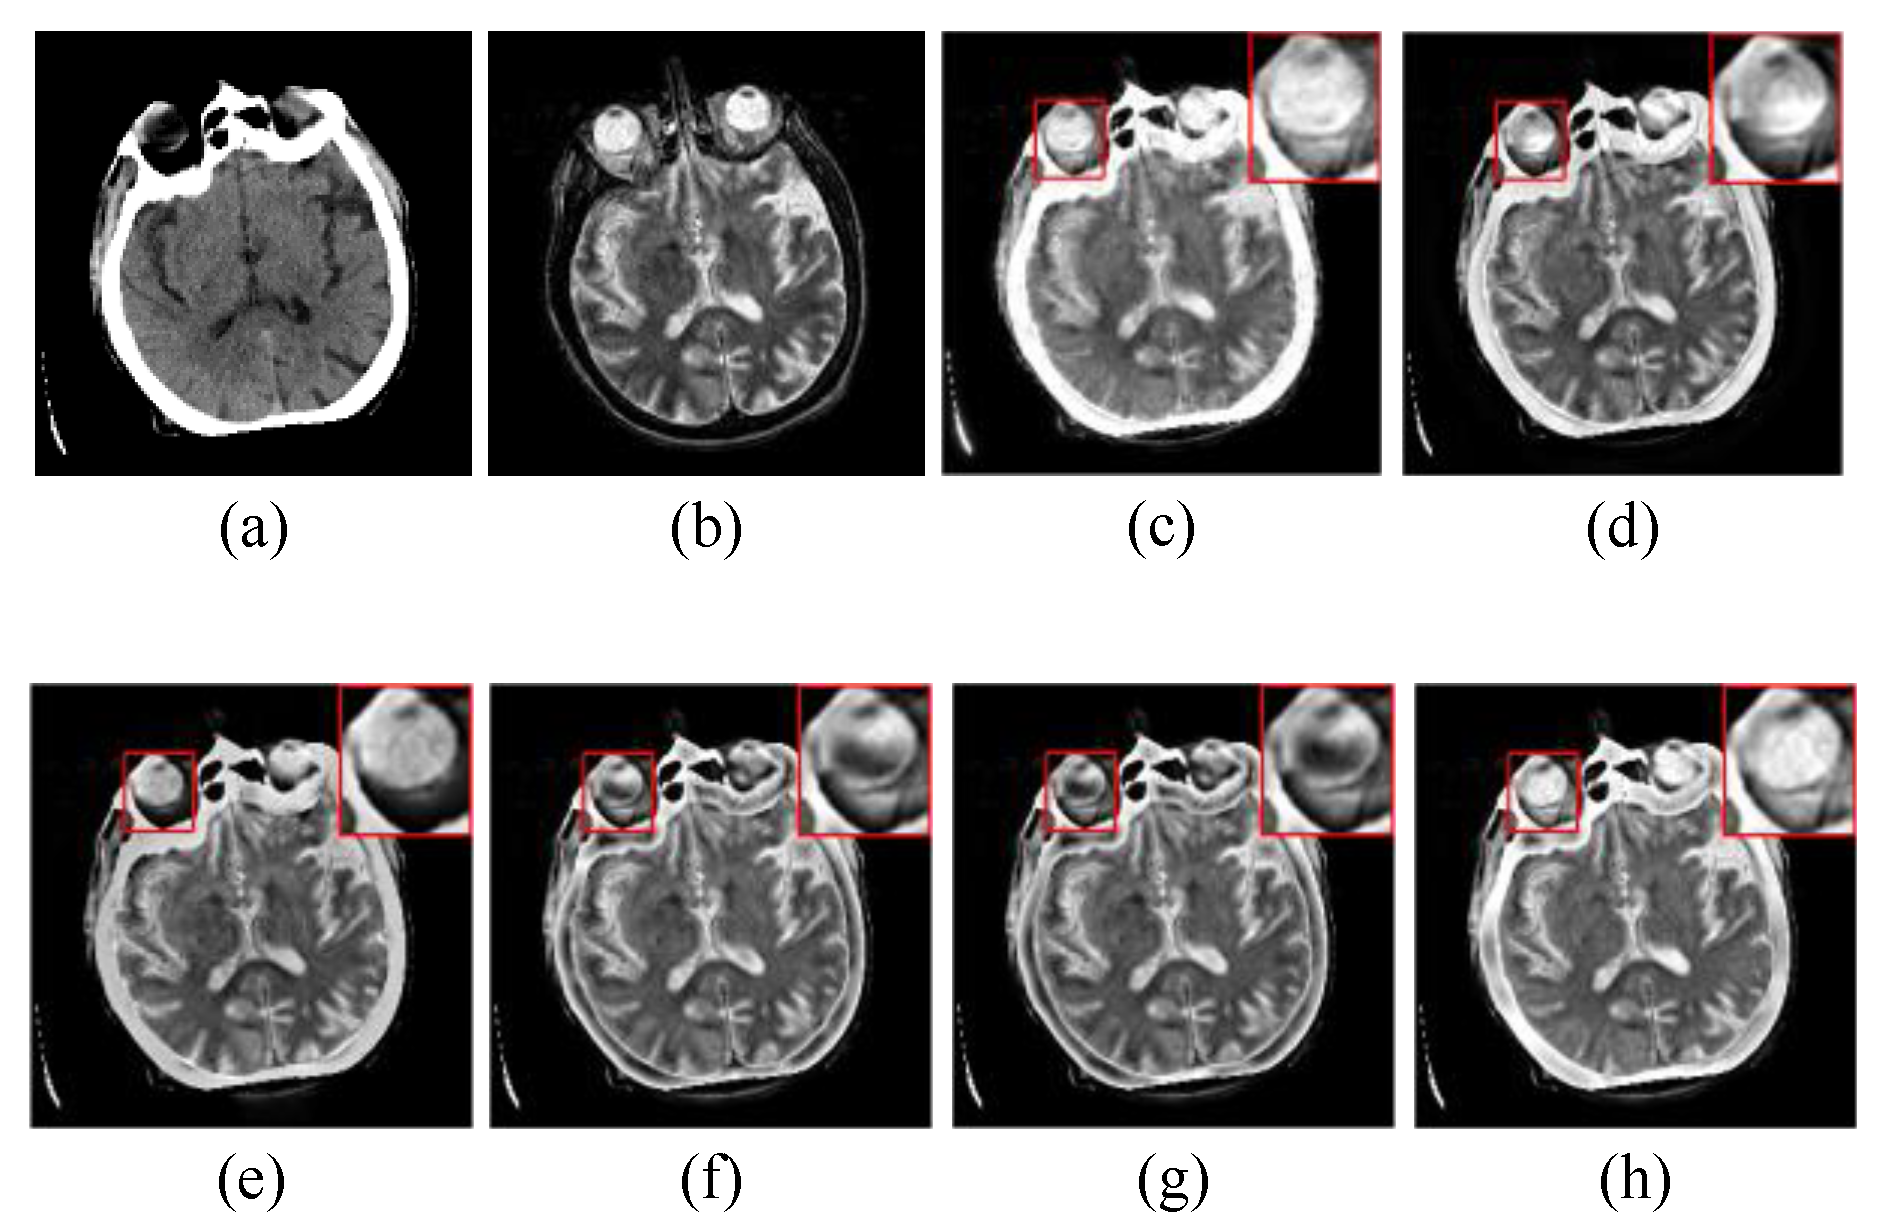

4.2.1. Subjective Visual Evaluation